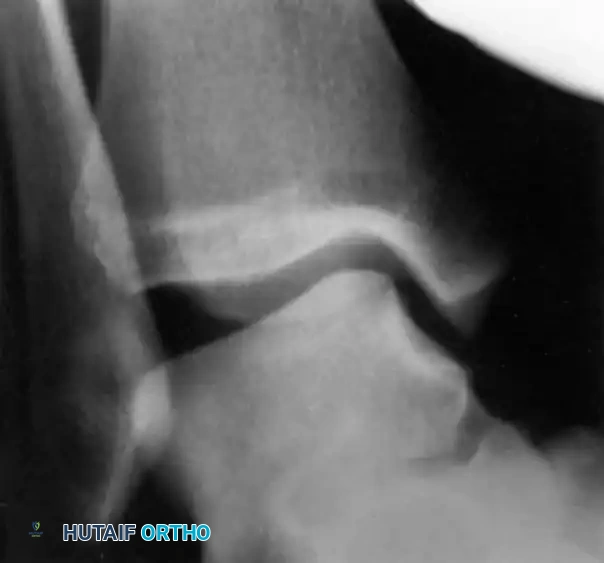

Inversion and Eversion Stress Tests (Talar Tilt)

Complete rupture of the deltoid ligament, including the deep portion, is rare in isolation. When the deltoid is completely ruptured in conjunction with a syndesmotic tear or lateral malleolus fracture, the talus shifts laterally with eversion stress.

If the lateral ligaments are completely disrupted, the talus tilts abnormally within the mortise under inversion stress. This stress is best applied with the ankle in slight plantarflexion to isolate the ATFL.

- Bonnin's Criteria: A talar tilt of 15 degrees indicates isolated ATFL rupture; 15 to 30 degrees indicates combined ATFL and CFL rupture; >30 degrees indicates rupture of all three lateral ligaments.

- Black's Criteria: Found no absolute clear-cut endpoint but noted that a talar tilt of less than 10 degrees is generally consistent with an isolated ATFL injury.